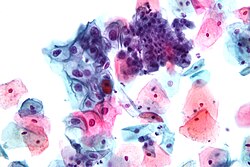

Od uzetog uzorka radi se citološki razmaz, koji se fiksira na mikroskopskoj pločici i boji po Papanikolauovoj metodi. Poslije bojenja vrši se mikroskopska analiza morfoloških osobina stanica, kojom se mogu otkriti znaci zapaljenja grlića, uzročnici infekcije, dobroćudne i zloćudne stanice i druge patohistološke promjene.

Papanikolauov test je metoda dopunskoga ispitivanja u okviru ginekološkoga pregleda, koja ima za cilj rano otkrivanje prekanceroznih i kanceroznih promjena stanica grla maternice, koje prethode karcinomu... „Od uvođenja Papanikolauova testa, stopa javljanja raka grla maternice pala je za oko 70 posto, a životi milijuna žena su produženi“[1]